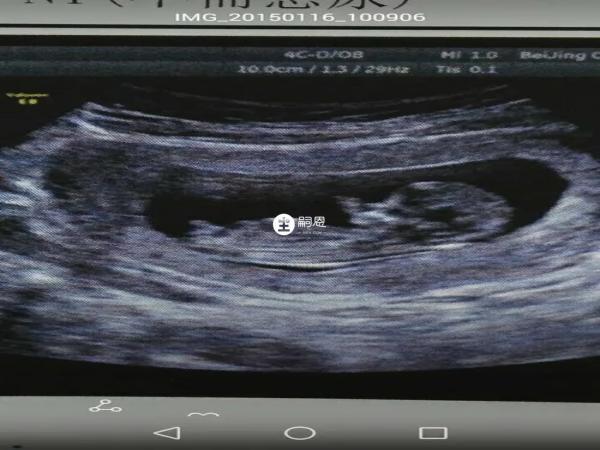

月經推遲10天以後可以去醫院進行B超檢查,確實是否有懷孕,B超檢查是確定早期妊娠快速而準確的方法,B超檢查可在增大子宮的輪廓中見到圓形的妊娠環,其內為液性暗,液性暗區內可見胚芽或胎兒,同時可見胎心搏動或胎動,除了驗孕需要做B超外,孕期還需要進行多次B超:

懷孕早期通常在7-8周進行一次超聲檢查,其目的是排出異位妊娠,同時還可以檢視胎芽以及原始心管的搏動,用以核對孕周。

早孕期間如果是做腹部B超,需要憋尿進行檢查,因為在懷孕早期子宮增大還不明顯,孕囊尺寸也比較小,子宮周圍被腸道所覆蓋,如果不憋尿,通過腹部B超看起來不清晰而導致誤診,而憋尿後膀胱充盈,可以把子宮周圍的腸道推開,使子宮暴露出來,可以清晰的觀察到子宮腔裡面的具體情況,就可以看到孕囊。